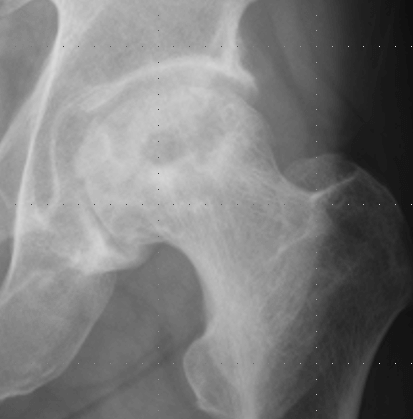

A:特発性大腿骨頭壊死症のA単純X線像(左)とMRIT1強調像(右).